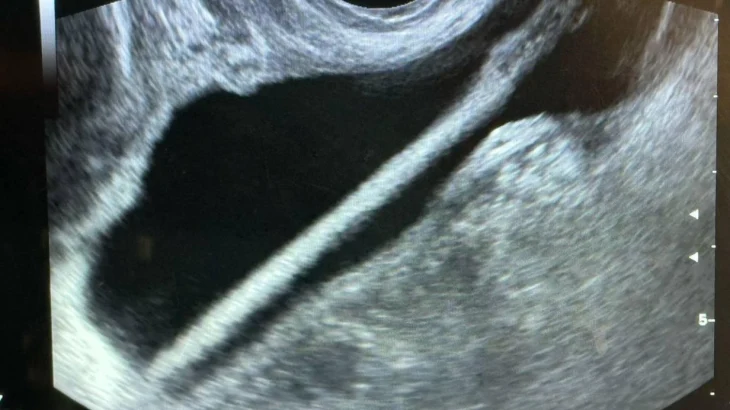

Как сообщил заведующий урологическим отделением Красногорской больницы Петр Сысоев, женщине сделали УЗИ, после этого провели операцию, в ходе которой удалили карандаш с помощью эндоскопа.